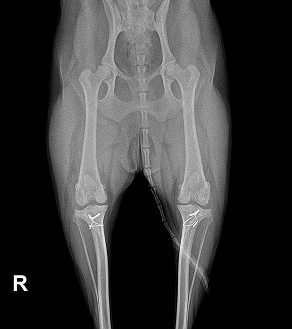

AFTER

BEFORE